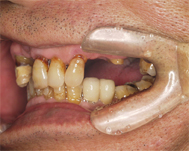

上顎にインプラント治療予定ですが、歯を支える骨も溶けて薄くなってしまっている状態でした。

この患者さんの歯茎はもうすでに腐り骨は溶けている状態だったので、骨を再生せずにインプラントを行なうと、写真のように歯茎の上の方からインプラントを入れることになり、非常に不自然な完成となってしまいます。